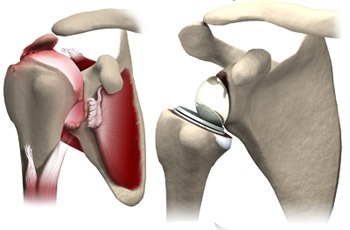

Knee replacement surgery is referred to as the surgical procedure that allows for replacing an arthritic or damaged knee with a metal, plastic, or ceramic device known as a prosthesis. This enables the patient to carry out movement similar to that of the healthy and natural knee. Although, the surgery can be performed to improve the conditions of the respective joint such as the ankle, wrist, shoulder, and elbow, knee and hip surgery are commonly performed joint replacement procedures. As the best orthopedic and joint replacement surgeon, Dr. B.R.Bagaria uses state-of-the-art techniques to help patients manage the various orthopedic disorders and knee-related problems. Moreover, patients with musculoskeletal and joint dysfunction or injuries are also provided quality treatment.

KNOW MOREHip replacement at Dr. Bagaria's Joint care by our Hip Replacement Doctor In Jaipur involves replacing the painful or arthritic hip joint with metal or ceramic and plastic components. It can be partial where only the ball of the hip is replaced or total where both the ball and socket of the joint is replaced.